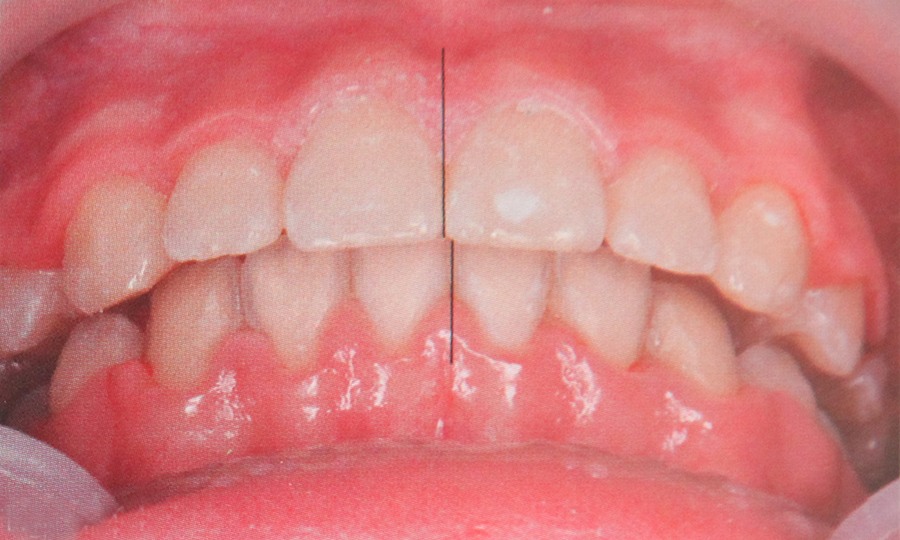

Se ocupa cu indreptarea pozitiei dintilor si a rapoartelor dintre acestia dar si a rapoartelor dintre oasele maxilare. Este foarte important sa se corecteze pozitia dintilor nu numai din motive estetice ci si functionale. Dintii inghesuiti nu pot fi igenizati corect si in timp se cariaza sau apar probleme parodontale. Rapoartele incorecte intre cele doua arcade provoaca tulburari care se manifesta prin oboseala musculara si dureri la mestecat.

Tratamentul  ortodontic poate fi realizat la orice varsta, dar este mult mai eficient la copii si adolescenti in perioada de crestere de aceea este recomandat un cosult de specialitate in jurul varstei de 10-12 ani. Insa si adultii pot beneficia de tratament ortodontic. In functie de tipul anomaliei prezente si de varsta pacientului tratamentul ortodontic poate varia de la cateva luni la cativa ani.